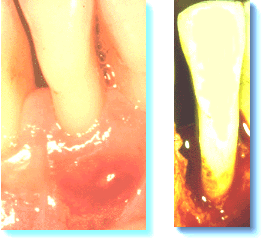

Mujer de 45 años de edad, que se queja de dolor a

las 3 semanas después del raspado y alisado radicular. Ella ha mantenido una

buena higiene oral en relación con el tratamiento. El margen

gingival había sanado y el tejido se adaptó estrechamente a la

supericie dental en la región coronal. Se observa una fístula

como resultado de un absceso periodontal. El diagnóstico clínico

de absceso periodontal era basado en el siguiente criterio:

Dolor que aumenta con el tiempo,

bolsa profunda al sondaje,

fluctuación del tejido blando en el lugar de

la inflamación

y salida de pus por la fístula o al sondaje de la

bolsa.

A veces el drenaje de pús no puede obtenerse a

través de la bolsa

periodontal y es necesario realizar un drenaje quirúrgico. La imagen

de la derecha se obtuvo en la cirugía y la causa del absceso puede identificarse claramente. Es importante intentar tratar la condición lo más pronto posible.

Debe eliminar el cemento infectado, cálculo y placa bacteriana, de lo

contrario el proceso continuará destruyendo tejido óseo y periodontal